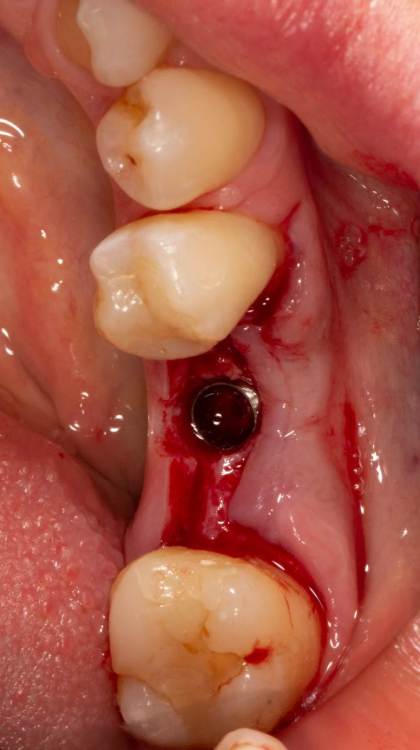

Женька Опубликовано 19 июня, 2023 Поделиться Опубликовано 19 июня, 2023 Здравствуйте, коллеги. Примерно с нового года начал ставить ТЛ имплантаты Дентиум. Что-то под заглушку (не поймал торки, представляете?). Что-то на низких формирвателях. И вот пришла пора протезирования, но отпустить к ортопеду не подготовив десну - не получается. Создал сам себе проблем, сегодня вот исправлял. Получилось неплохо? 3 Ссылка на комментарий

Женька Опубликовано 20 июня, 2023 Автор Поделиться Опубликовано 20 июня, 2023 @АнтонТЛТ мы же позиционируем платформу относительно зенита? Есть ли разница тогда, какой имплантат мы выбираем? Вообще весь смысл здесь был заложен в том, что толщина гребня была не очень. Хотелось поставить тонкий имплантат 3.6. Но рисковать тонкой платформой не хотелось, поэтому выбор пал на 4.8 платформу ТЛ и тело имплантата 3.6 1 Ссылка на комментарий